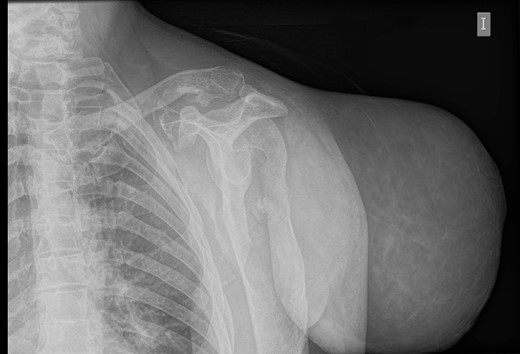

An initial study was performed at the emergency department to dismiss extended disease in case of final proven malignancy. The laboratory results were within normal values; no anaemia was detected. Simple radiography described a giant soft tissue tumour and bone deformities compatible with osteochondromatosis (Fig. 2). The CT scan described a voluminous tumour of adipose tissue in the scapular region of the left shoulder together with other bone lesions compatible with multiple osteochondromatosis. No metastases were described in this study. The patient was discharged with oral antibiotics and the use of a shoulder sling to prevent further complications due to the weight of the tumour.

Simple radiography: evident soft tissue tumour on the left shoulder with multiple bone deformities compatible with osteochondromatosis.